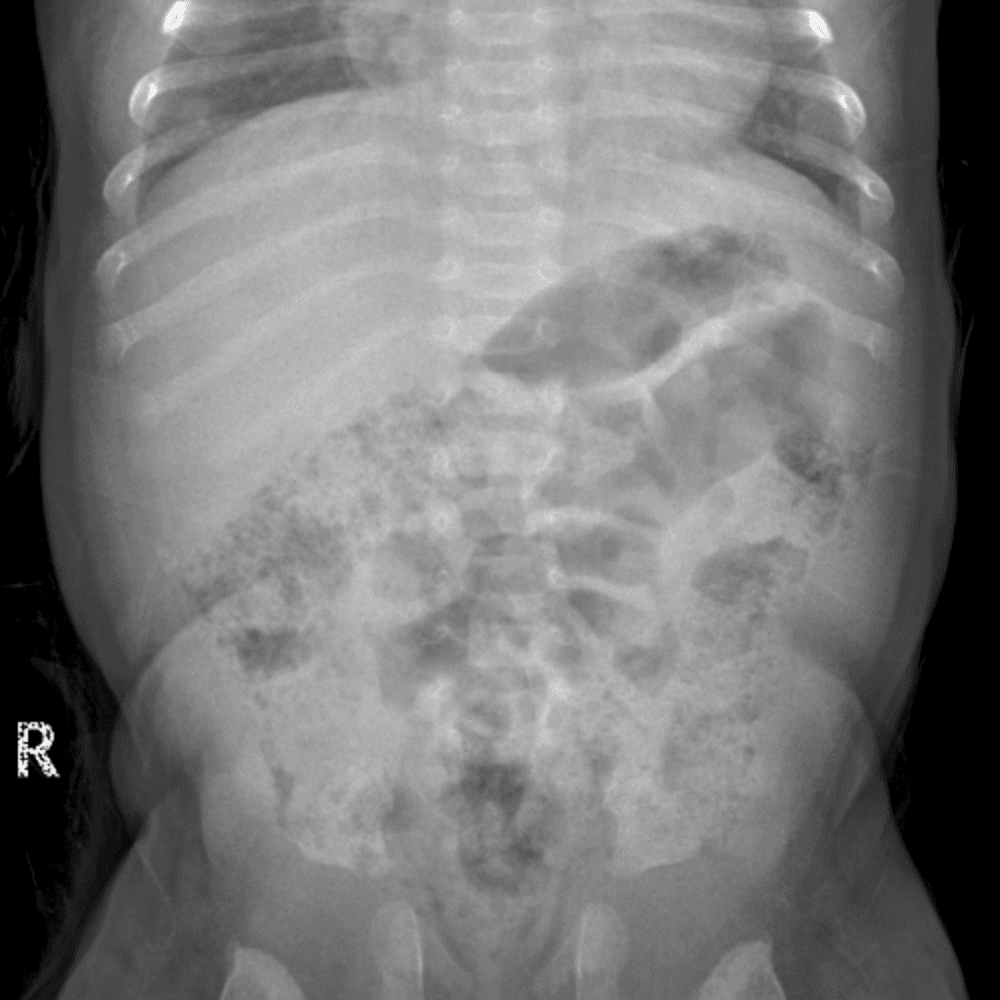

Peds Abdomen

Practice

Simulates call by including subtle or difficult cases and some normals.

30 cases